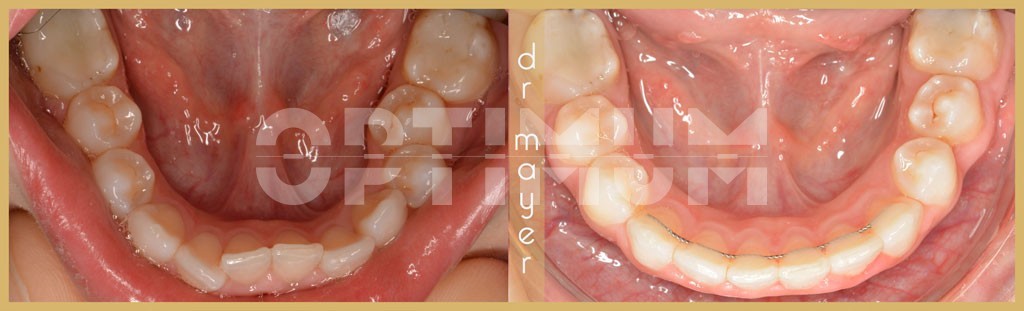

Páciensünk esztétikai fogszabályozás céljából kereste fel a rendelőnket. A kezelési terv elkészítése után nem csak a felső kiálló kismetszőfog/befelé álló nagymetszőfogakat és a torlódásokat, hanem súlyos mélyharapást, az alsó állcsont hátraszorulását találtuk és jobb oldalt keresztharapást találtunk.

A funkcionális helyreállítással, a harapás megemelésével és alsó állcsont átpozicionálásával láthatóvá váltak az alsó fogak is, ami nagyon sokat javít az összképen és hosszútávon az állkapocsízület is hálás lesz.